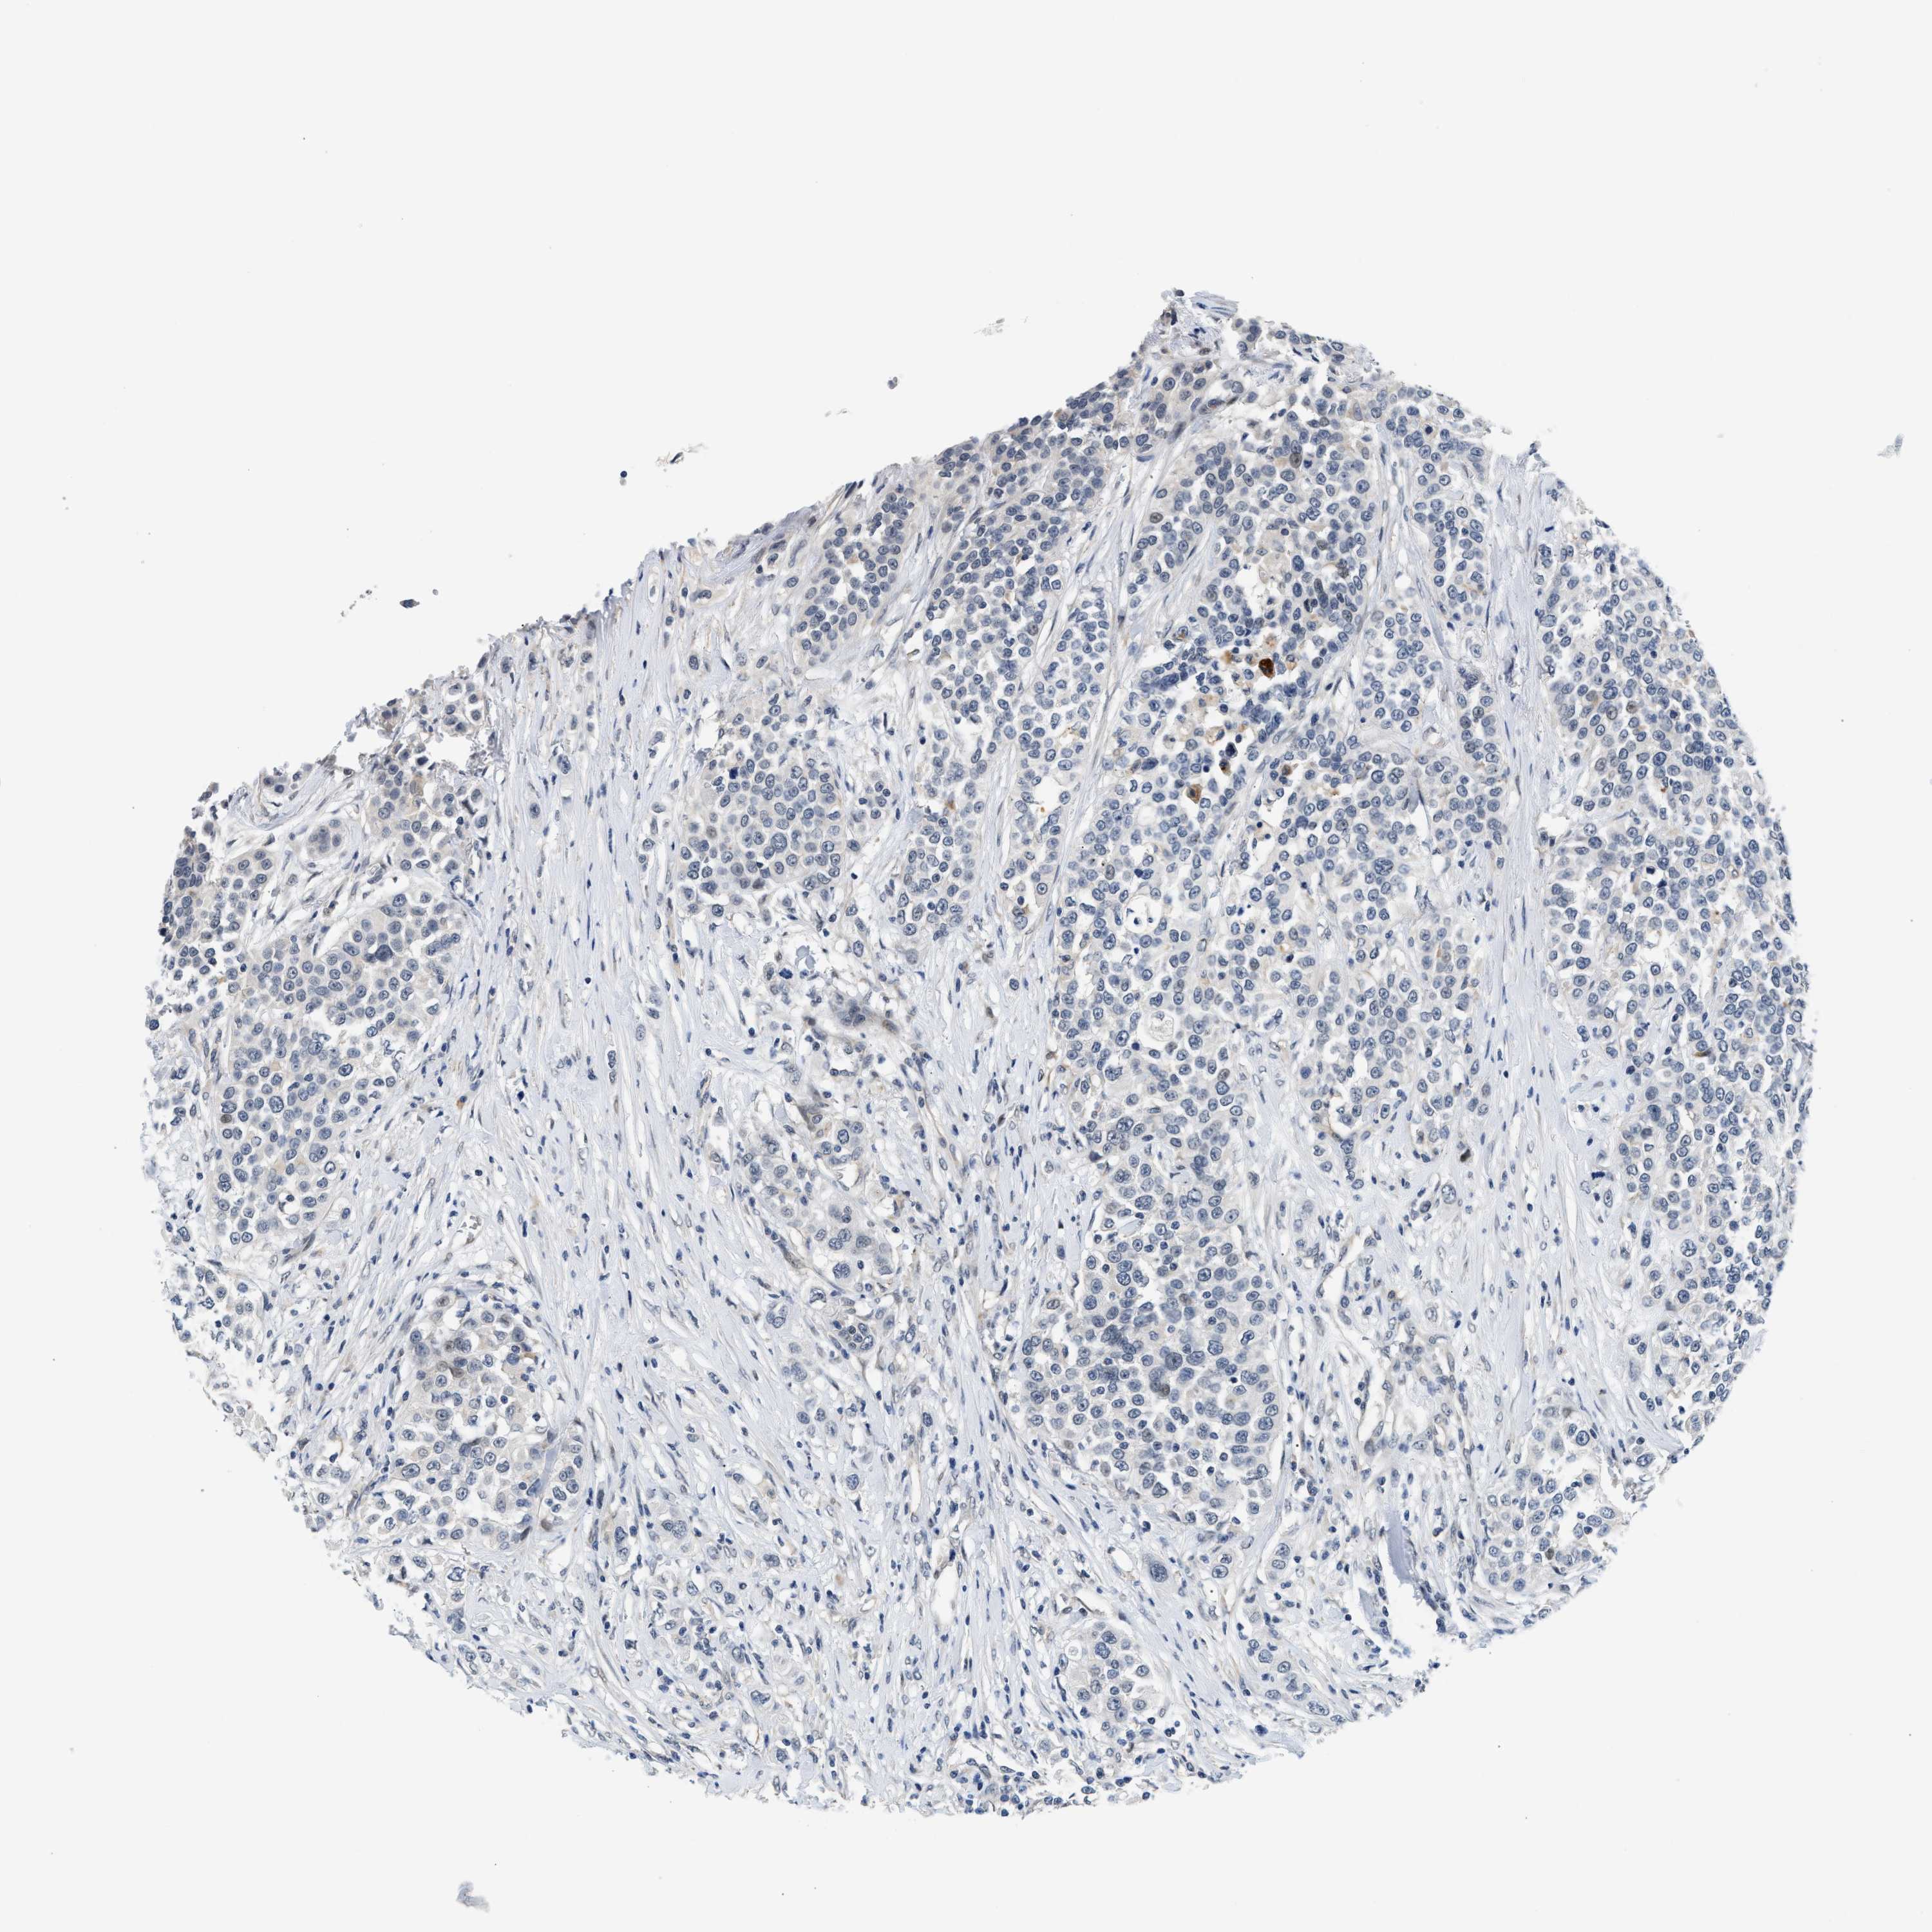

UROTHELIAL CANCER - Protein expressioni

A mouse-over function shows sample information and annotation data. Click on an image to view it in a full screen mode. Samples can be filtered based on level of antibody staining by selecting one or several of the following categories: high, medium, low and not detected. The assay and annotation is described here.

Note that samples used for immunohistochemistry by the Human Protein Atlas do not correspond to samples in the TCGA dataset.

Antibody stainingi

Antibody staining in the annotated cell types in the current human tissue is reported as not detected, low, medium, or high, based on conventional immunohistochemistry profiling in selected tissues. This score is based on the combination of the staining intensity and fraction of stained cells.

Each image is clickable and will lead to virtual microscopy that enables deeper exploration of all samples and also displays staining intensity scores, fraction scores and subcellular localization as well as patient and tissue information for each sample.

Antibody HPA044244

Antibody HPA058777

Antibody CAB020694

Staining

High

Medium

Low

Not detected

Intensity

Strong

Moderate

Weak

Negative

Quantity

>75%

75%-25%

<25%

None

Location

Nuclear

Cytoplasmic/membranous

Cytoplasmic/membranous,nuclear

Urothelial carcinoma, High grade

Urothelial carcinoma, Low grade

Urothelial carcinoma, NOS